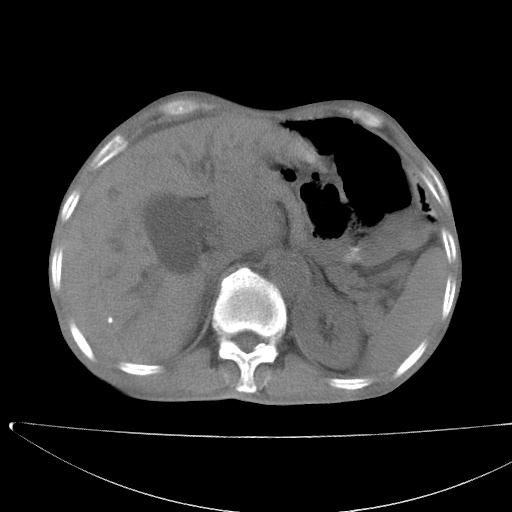

标题: CT17147:男70岁,上腹部不适1月。 [打印本页]

患者男70岁,上腹部不适1月。8年前有胃癌手术史。余病史不祥。

考虑胃癌复发并小网膜淋巴结转移侵及肝脏胆总管梗阻

考虑胃癌复发并腹腔内淋巴结转移。

1)胃癌术后,复发不排除。

2)肝脏转移瘤。

3)肝脏钙化灶。

4)胆囊增大。

5)腹膜后多发性淋巴结转移。

6)腹水。

7)右侧少量胸水。

建议:增强扫描。

1)胃癌术后,不排除复发可能。2)考虑肝脏及腹膜后淋巴结转移瘤。3)肝内胆管扩张,胆囊增大。4)肝内胆管结石(或钙化)。5)脾脏钙化灶。6)腹水。7)右侧少量胸腔积液。

建议:行ct增强扫描检查。

1、胃癌根治胃空肠吻合术后,残胃癌?

2、肝门区占位性病变并胆道上段梗阻(肝内胆管扩张、胆囊增大),考虑肝门区淋巴结转移累及胆总管,建议ct增强扫描;

3、右侧胸腔少量积液、少量腹水;

4、肝右叶胆管结石。

肝门区占位性病变并肝内胆管扩张。

小网膜囊区及腹膜后肿大淋巴结。